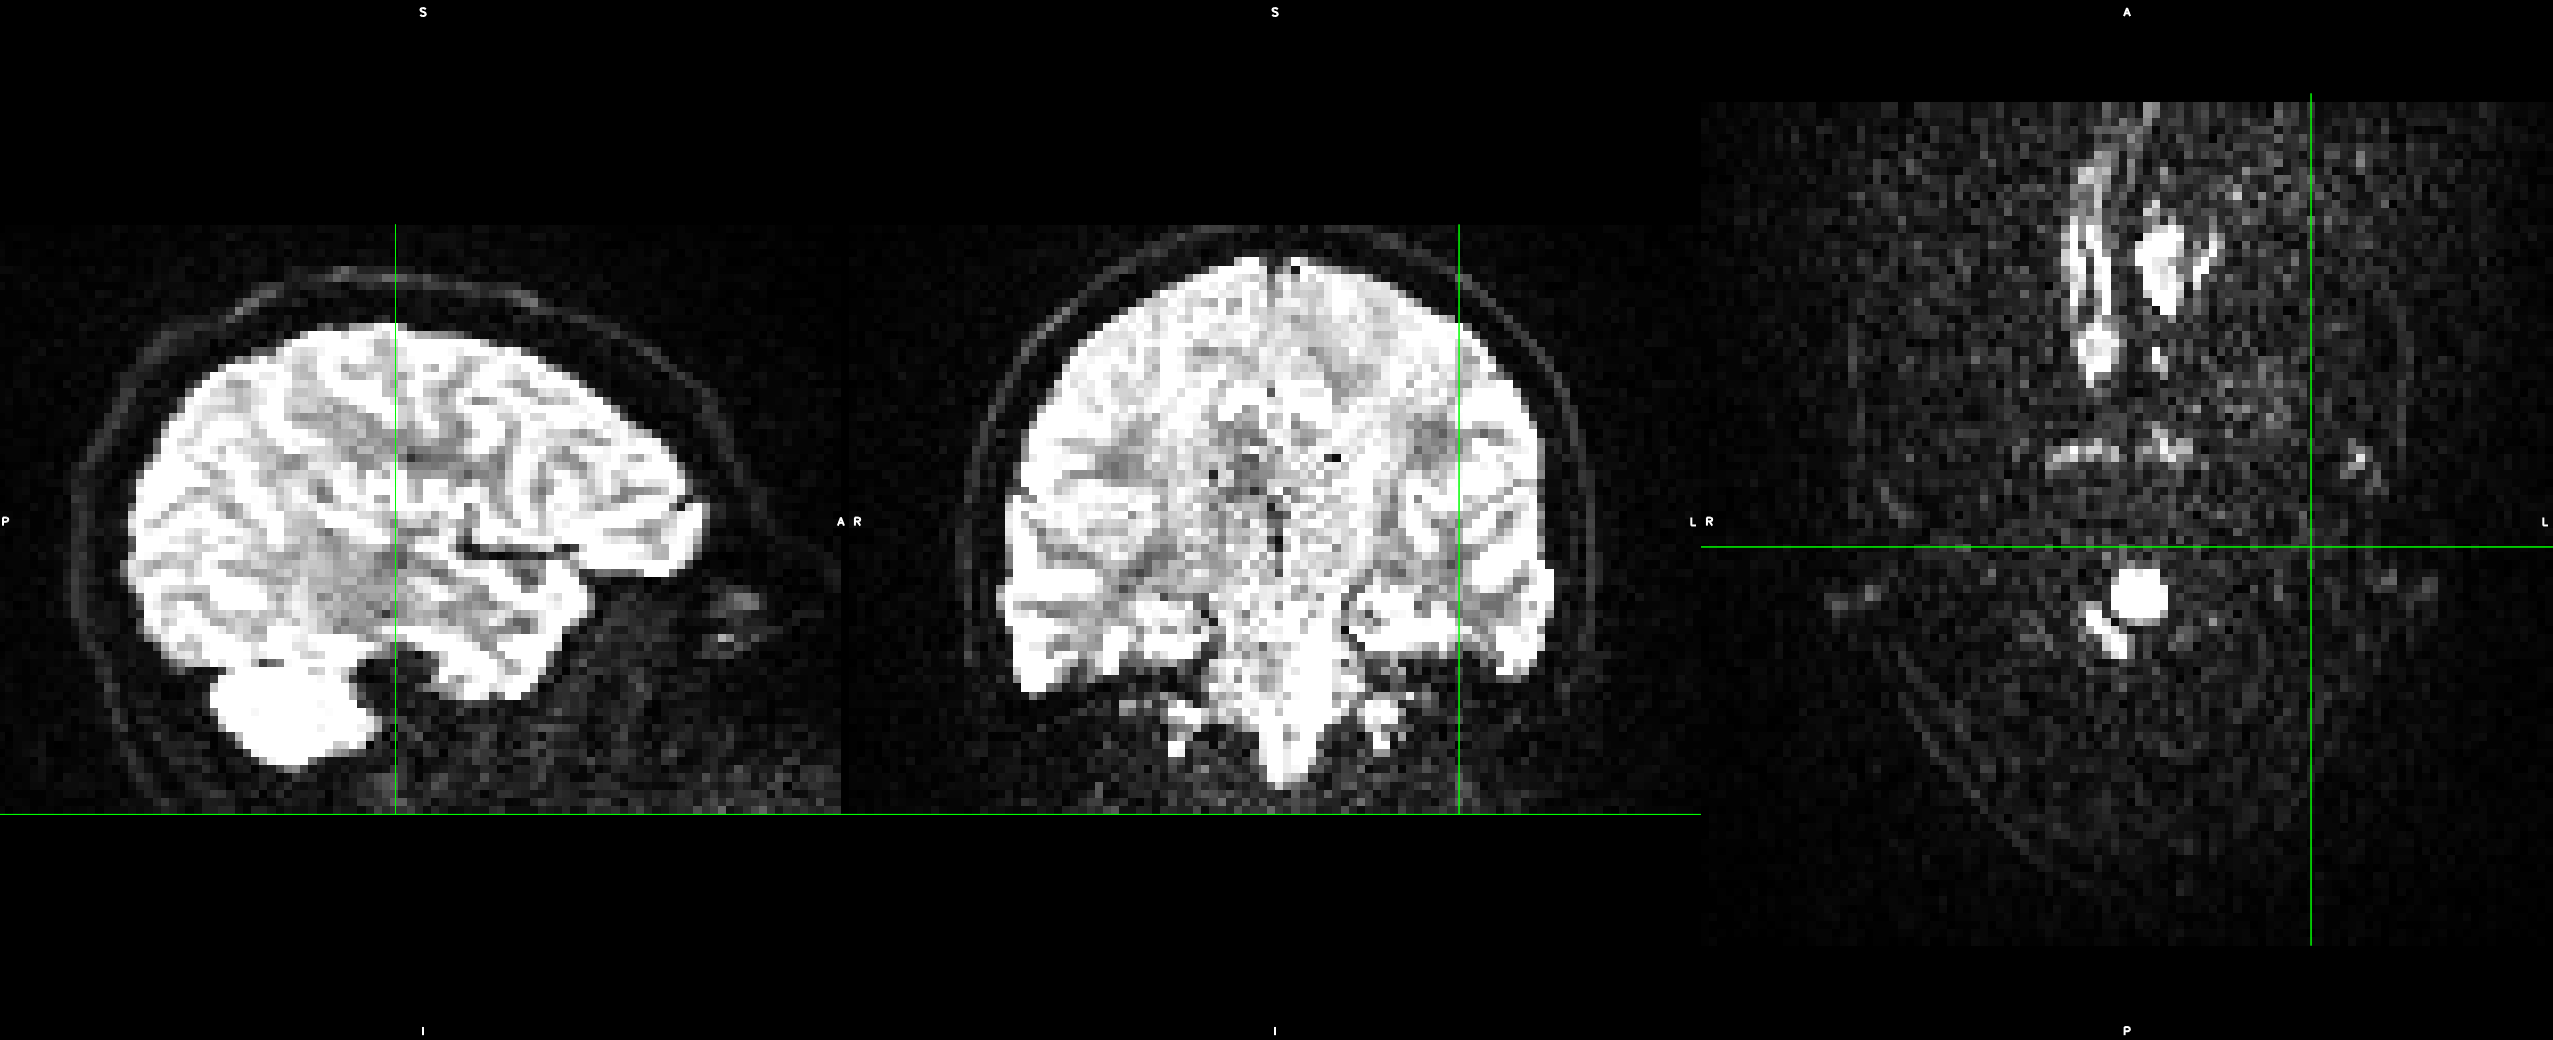

Subject movement correction and B-matrix reorientation are done using the freely available FSL tools jenkinson2002improved and the DIPY imaging library garyfallidis2014dipy , respectively. A practically relevant implementation detail concerns boundary effects. As illustrated in Figure 5, missing information can enter the field of view when applying image transformations. We found that q-space inpainting near the boundary of the domain works more reliably if we resolve these cases with nearest neighbor extrapolation, rather than with zero padding.